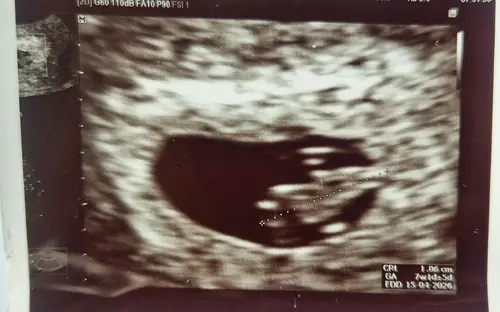

Gefeliciteerd! 🩷🩵 dat is een mooie echo!

Wij hebben gister een superecho gehad met 7+5 (maar gemeten op 8+1 dus weer een paar daagjes erbij gekregen 🥰). Bij onze vk laten ze ook al hartje horen vanaf 8 weken, maar wel heel kort. Maar we hebben een usb stickje met een filmpje ervan dus ik kan er nu constant naar luisteren ! ❤️

Ik ben vandaag 8+1, heb vorige week woensdag een mooie echo gehad met een kloppend hartje en geschat op 7+5 toen. ☺️

Ik heb hier ook wel behoefte aan! Ik zat op het punt om mijn account te verwijderen door alle, meeste, negatieve topics. Als ik die zie open ik ze meestal ook automatisch gewoon wat ik wil vermijden. Ik ben volgens berekening 7+2. Vorige week al een echo gehad en een kloppend hartje gezien😊. Vrijdag weer een echo bij de verloskundige, ik hoop zo erg dat het goed blijft gaan!